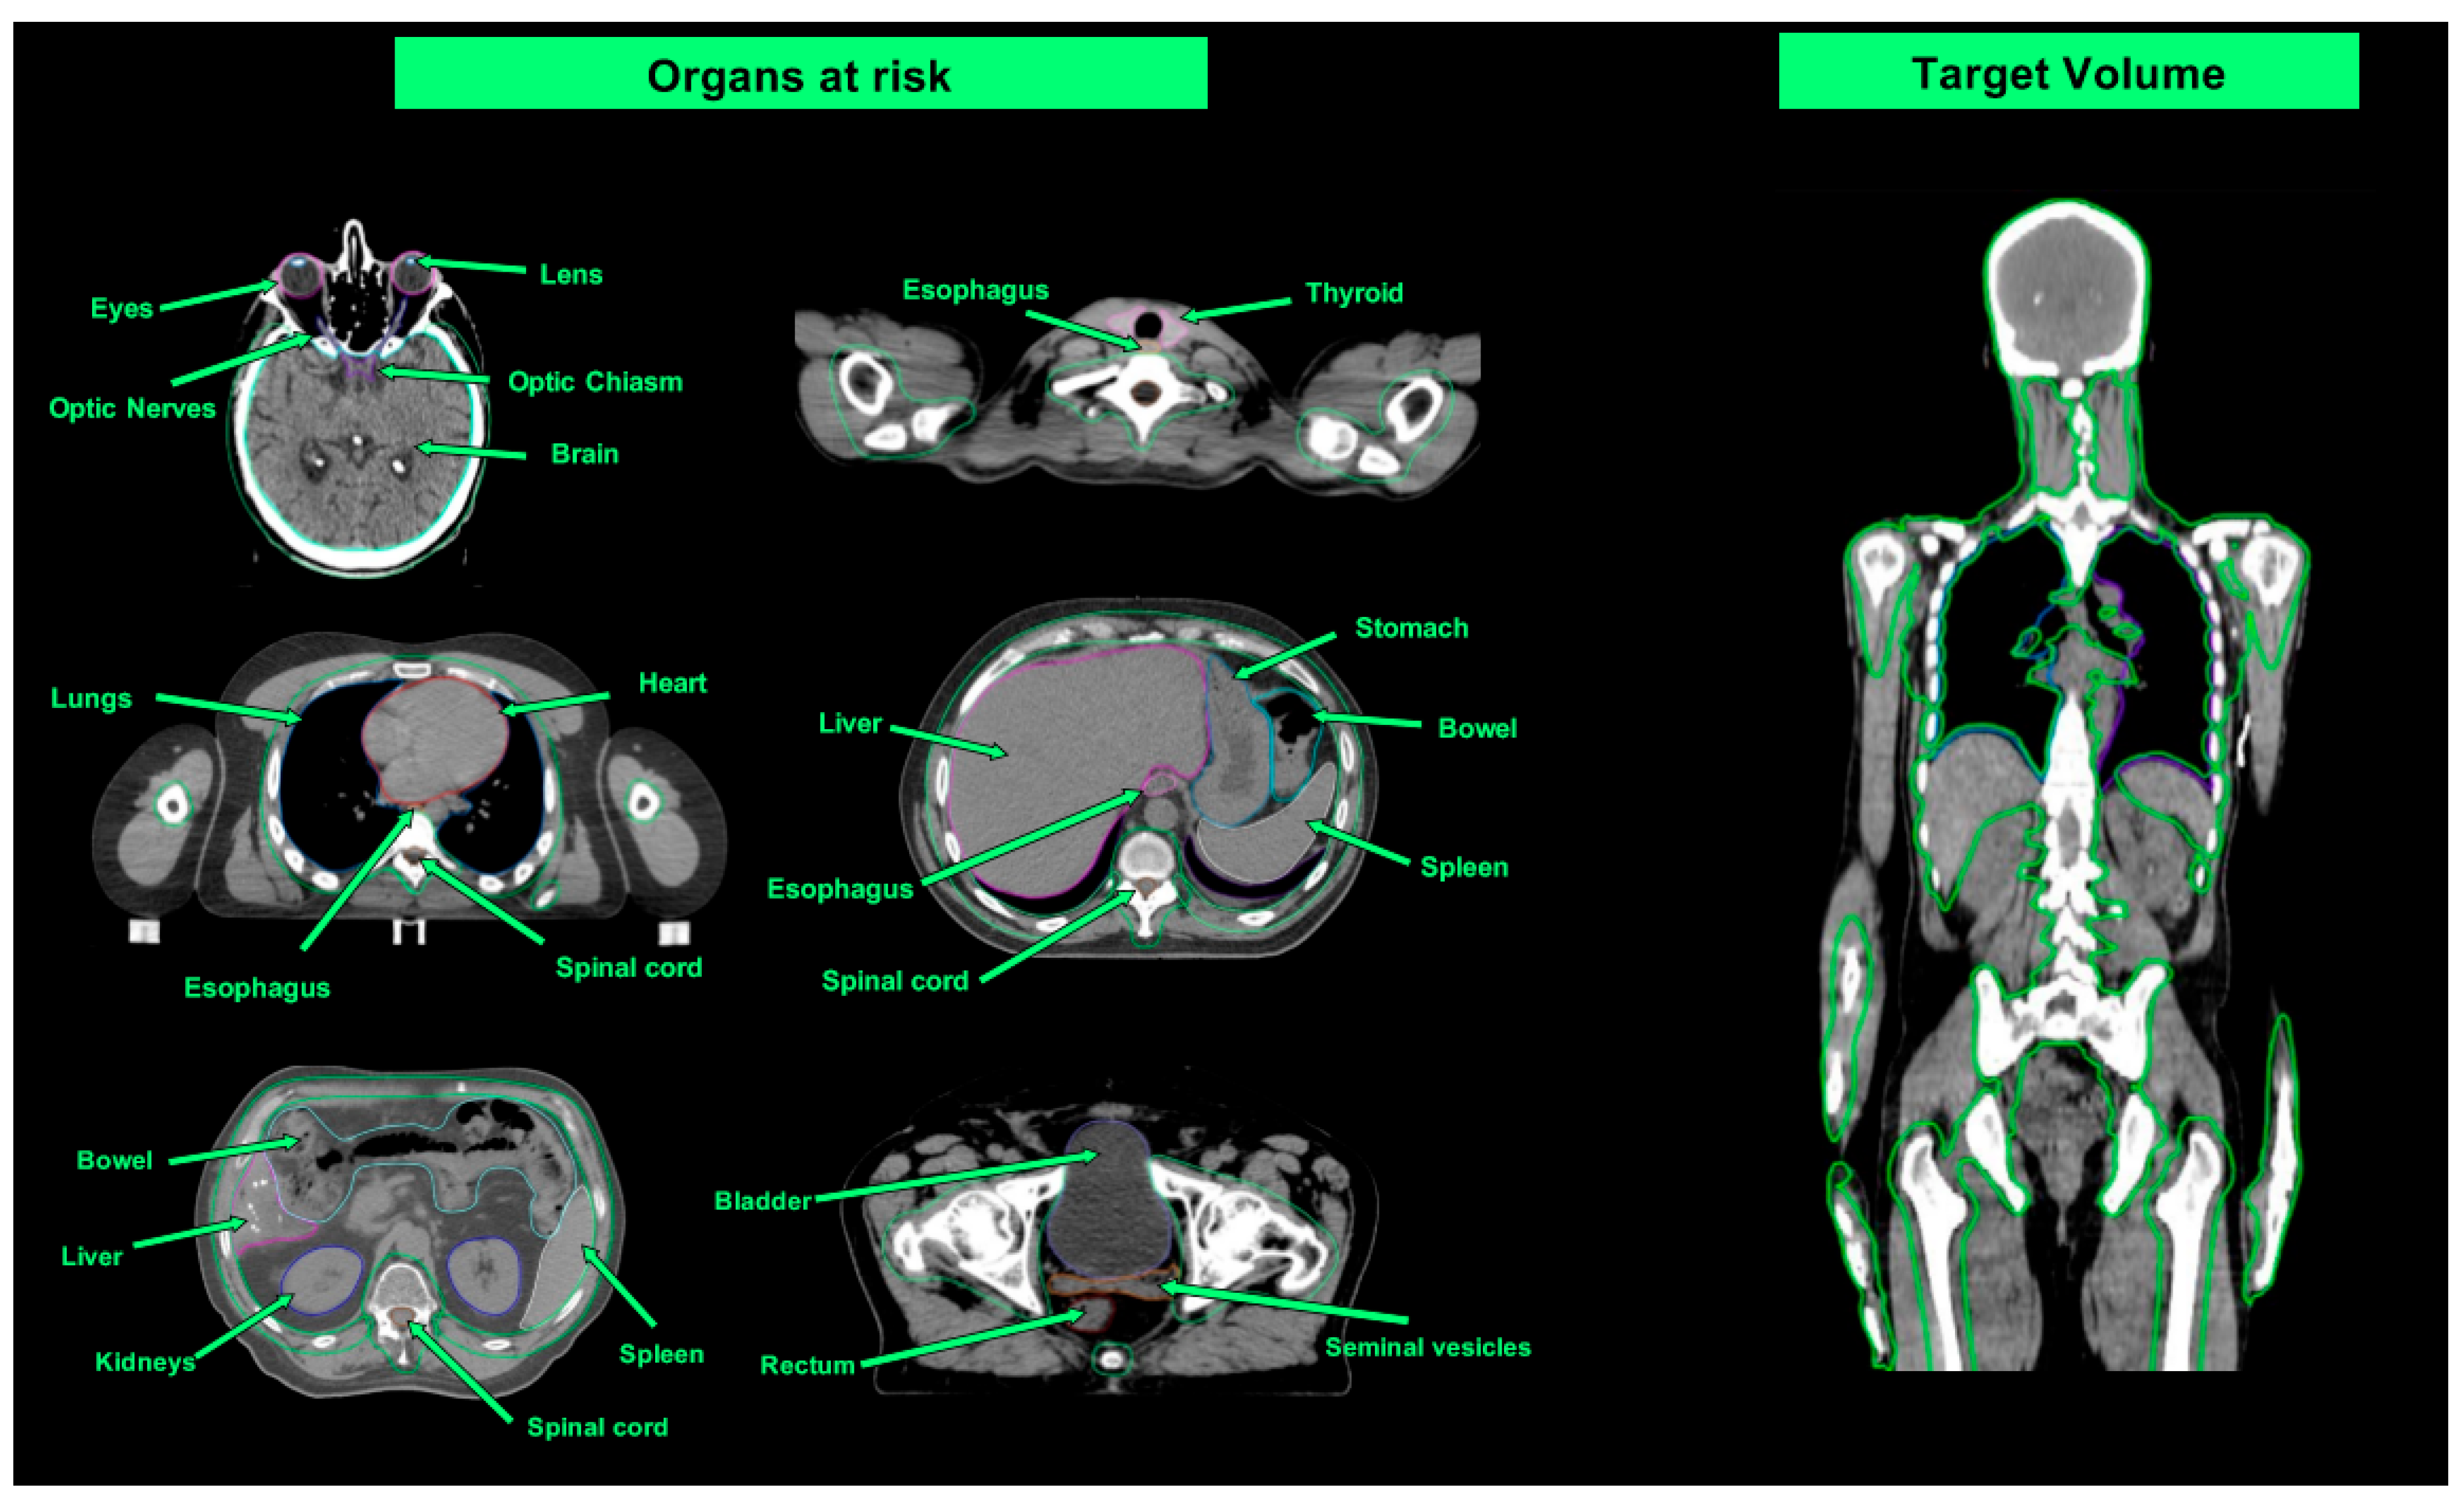

4.1. Planning

4.3. Treatment Delivery

| Organ at Risk | TBI Median Doses (Gy) | Studies Evaluating TMI/TMLI Median Doses (Gy) | ||

|---|---|---|---|---|

| Wong et al. [51] (TBI 12 Gy) | Wong et al. [51] (TMI/TMLI 12 Gy) | Wong et al. [51] (TMI/TMLI 20 Gy) | Our Case (TMLI 12 Gy) | |

| Brain | 12.0 | 4.0 | 7.9 | - |

| Lens | 11.3 | 1.5 | 1.9 | 1.7 |

| Eyes | 11.3 | 6.6 | 7.0 | 5.7 |

| Optic nerves | 12.4 | - | - | - |

| Oral cavity | 11.8 | 3.9 | 4.8 | 8.5 |

| Parotids | 11.8 | 3.9 | 4.8 | 9 |

| Thyroid | 12.1 | 3.7 | 4.9 | 3.9 |

| Esophagus | 12.4 | 3.9 | 5.6 | 11.7 |

| Breasts | 11.5 | 6.9 | 8.7 | - |

| Lungs | 8.9 | 4.3 | 6.8 | 7.7 |

| Heart | 12.1 | 6.2 | 6.4 | 6.1 |

| Stomach | 12.2 | 3.1 | 5.0 | 5.5 |

| Small Intestine | 12.5 | - | - | 5.7 |

| Liver | 12.3 | 6.0 | 8.7 | - |

| Kidneys | 12.2 | 5.6 | 8.7 | 5 |

| Bladder | 12.4 | 7.0 | 7.4 | 6 |

| Rectum | 12.6 | - | - | 5.9 |